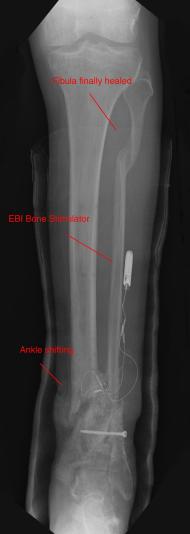

Postoperative (12th) images of left ankle

The images displayed here were created at various appointments following surgery performed by Dr. Daniel Saunders. In the X-Ray you can see

where Dr. Saunders has removed the fibula plate, joined the tibia and fibula with a screw, built-up the area of the tibia where previously

there was considerable absence of bone and lastly added the EBI OsteoGen-M Bone Stimulator (dual lead). The photos show the left side site

where the fibula plate was removed, the top site where donor bone, bone filler material and the stimulator were added and the right side

where the tissue has burst because of swelling. Liam was placed on an IV drip of Vancomycin following surgery to combat the potential onset

of Osteomyelitis. The image of the cast includes the fibula plate that was removed during surgery. The next images were taken later and show

that the staples and stitches were removed. In one of the images, you can see Liam's wife Madeline helping with leg cleanup and in one image

can be seen the EBI representative after being put to work (holding up the left leg while the latest cast cures) by Dr. Saunders. Later shots show

a healing tissue burst site with some overgrowth and Dr. Saunders cauterizing the overgrowth. Bones shifting too much (shown in X-Rays). The

last images are of the left ankle prior to the 13th surgery.